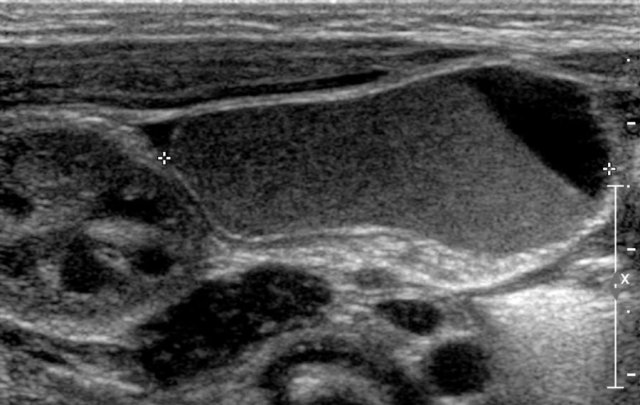

The US- image shows a cystic lesion in the lower abdomen in a 3-year-old girl with colicky abdominal pain.

At operation a torsion of the right adnex was seen.

On pathology a teratoma was demonstrated.